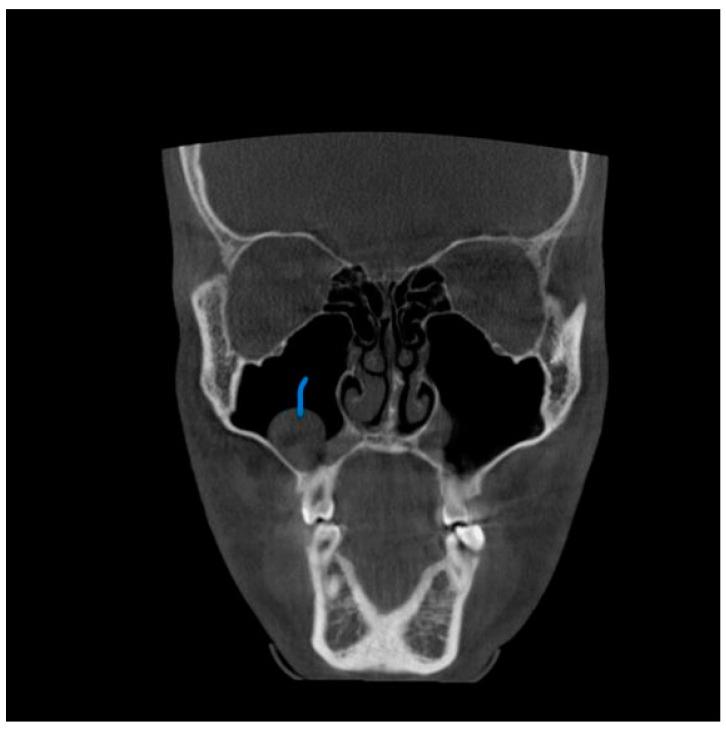

尽管锥形束计算机断层扫描(CBCT)在区分软组织方面存在局限性,但它对牙科手术产生了重大影响,并给我们的诊断和治疗计划方法带来了重大变革。它是一种出色的成像方式,能快速识别鼻窦混浊,并为鼻旁窦病变提供有价值的见解,且辐射暴露量低得多。本研究旨在调查CBCT扫描中上颌窦异常的发生率,确定这些发现的频率、类型和位置,并找出根尖周病变距离与上颌窦影像学变化之间的相关性。两名检查人员独立评估了117例患者,以诊断并将病例分类为不同的异常亚型。记录与鼻窦关系最密切的根尖周病变。记录左右上颌窦口的直径以及窦口下缘至鼻窦骨底的距离。将这些发现与这些患者的年龄和性别相关联。本研究表明,61例患者被诊断为黏膜增厚(52.1%)。受黏膜增厚影响最大的鼻窦壁是上颌窦底,其次是内侧壁和外侧壁。在19例有根尖周病变的患者中,15例有上颌窦黏膜增厚,这具有统计学意义(P = 0.004)。上颌窦异常的高发生率强调了放射科医生全面解读CBCT图像中获取的整个容积(包括整个鼻窦)的重要性。偶然发现可在个体的症状和体征临床背景中予以考虑,以降低高估影像学发现实际影响的风险。

https://cdn.ncbi.nlm.nih.gov/pmc/blobs/9100/10528184/b05bf2d0387e/diagnostics-13-02918-g001.jpg